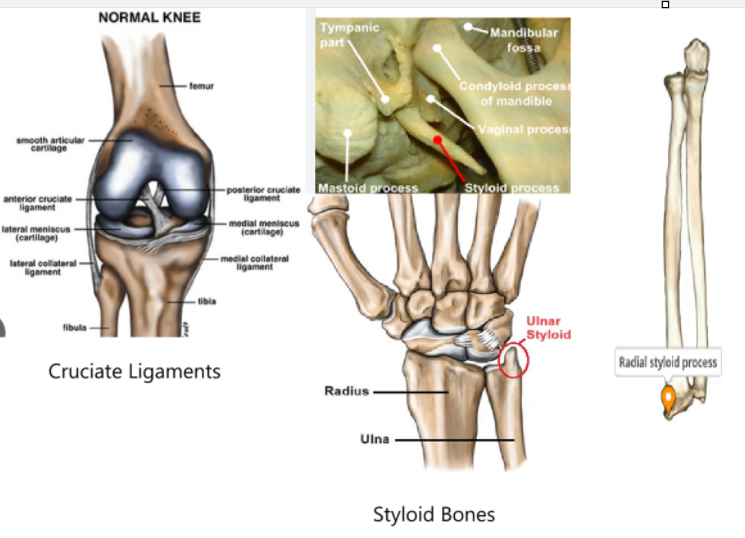

The two large bones that help to form the majority of the adult pelvis are the:

a. cruciate bones

b. styloid bones

c. innominate bones

d. sesamoid bones